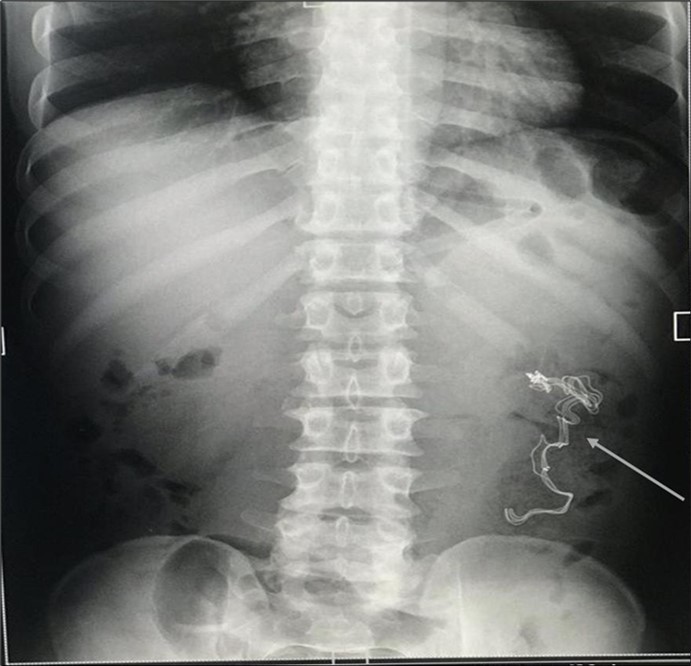

An impression of an intestinal obstruction due to postoperative adhesions was made. An abdominal X-ray done showed no obvious signs of bowel dilatation but an ill-defined opacification in the area of the left lumbar region (Figure 1). An ultrasonography done showed an echogenic mass in the left iliac region measuring about 4.1cm in diameter. There was no flow on colour doppler interrogation (Figure 2). At this point a diagnosis of foreign body was queried. The patient was counselled and prepared for exploratory laparotomy.

Figure 1.Erect abdominal X-Ray showing an ill-defined opacification in the left lumbar region (arrowed).